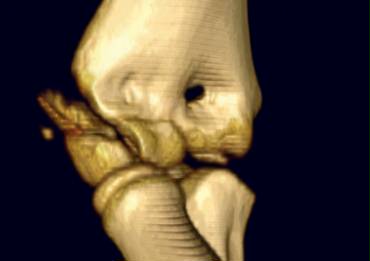

Since most of the structures involved are cartilageneous, it is very difficult to know the exact extent of the fracture.

CT reconstruction of displaced lateral condyle fracture. Humeroulnar joint is stable. CT reconstruction of displaced lateral condyle fracture. Humeroulnar joint is stable.

Sometimes the fracture runs through the ossified part of the capitellum. In those cases it is easy.

The case on the left shows a lateral condyle fracture extending through the ossified part of the capitellum.

This is a Milch I fracture. The elbow is stable.

There is too much displacement so osteosynthesis has to be performed.